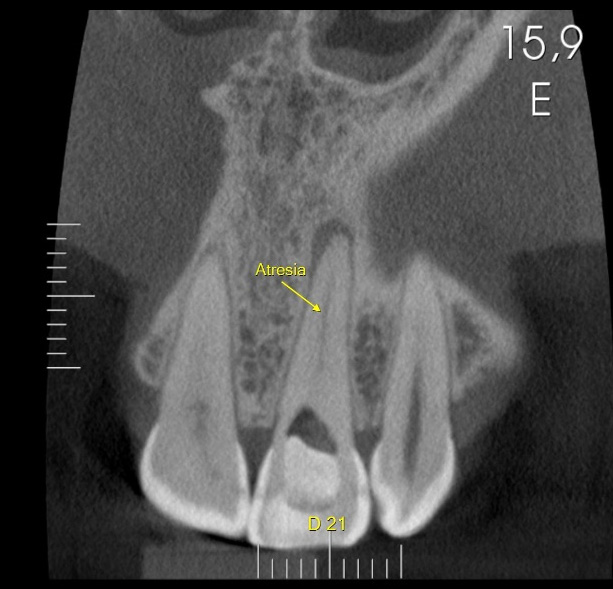

Patient I.N.A.A., 29 years old, female, came to the Escola De Ensino Educação Inteligente (EI Uningá – Londrina, Paraná) after being treated at a private clinic. The patient reported that a routine radiographic examination was performed, and the dentist identified a periapical lesion in tooth 11, in addition to darkening of its color. Endodontic treatment of the tooth was then proposed. At the same location, an attempt was made to access the pulp, but without success. She was referred for a CT scan (Figures 1A and 1B).

Figure 1: Tomographic image, sagittal section (B)